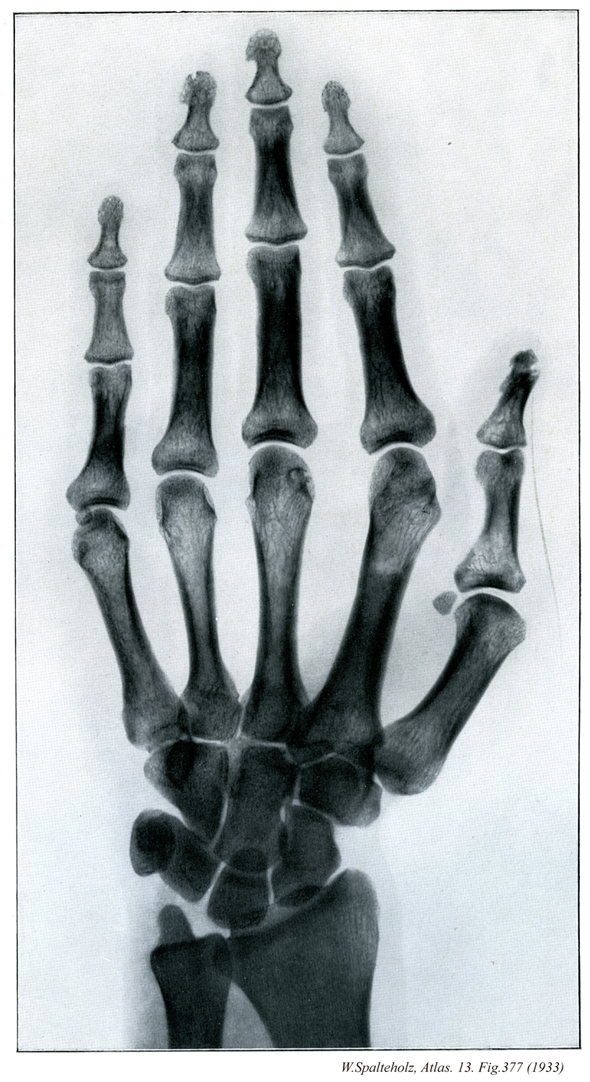

377

【Hand

手;テ

Manus】

→(手は上肢のうち橈骨手根関節より遠位の部分。手根と中手に区別され、手根と中手の前面を手掌、後面を手背という。皮膚節において第六頚神経、第七頚神経、第八頚神経のレベル。)